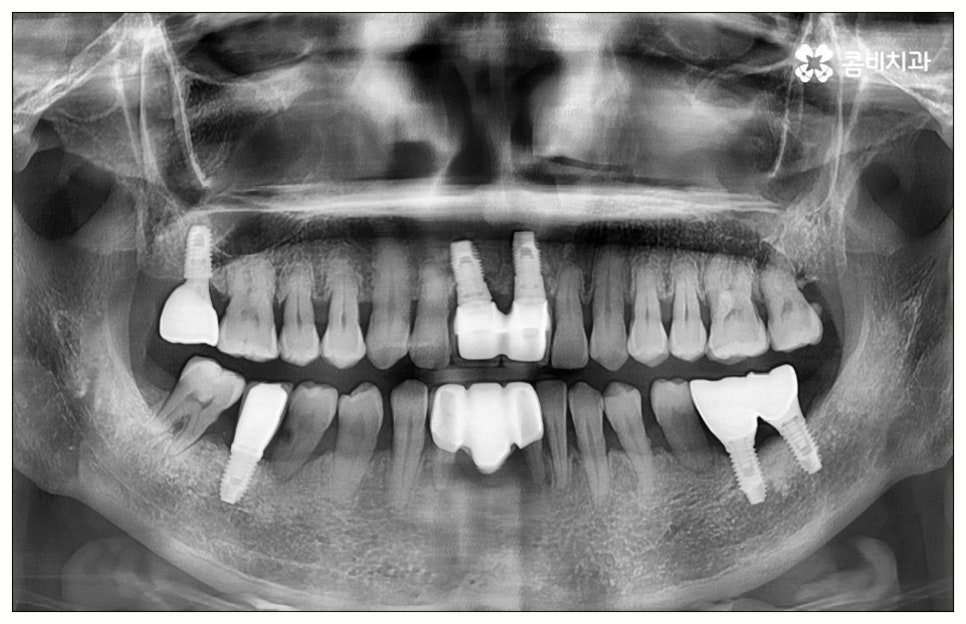

특히 임플란트 기술의 꽃이라고 할 수 있는 원데이임플란트 방식을 이용하면 발치부터 식립, 임시치아 장착까지 하루 만에 가능하기 때문에 비교적 긴 치료 기간이나 잦은 내원에 따른 어려움, 통증에 대한 두려움 등 환자분들이 느끼는 여러가지 부담을 많이 줄여줄 수 있어요. 치아 상실과 동시에 원데이임플란트 시술을 받으면 치아 공백 기간을 줄여 치조골이 위축되는 것을 방지해 주어 뼈 보존 측면에서도 유리하며, 특히 앞니와 같이 입을 벌렸을 때 잘 보이는 위치에 있는 치아를 상실한 경우 원데이임플란트 를 이용하면 빠른 수복이 가능하기 때문에 일상 생활에서 겪는 불편이 크게 감소할 거예요.

이때 만약 무리하게 즉시 식립을 진행하게 되면 임플란트 치아가 제대로 기능하기 어려울 뿐 아니라 주위염 등 부작용을 일으킬 가능성이 높아 주변 잇몸 및 치아에도 좋지 않은 영향을 주게 되며 결국 임플란트가 흔들리거나 빠지면서 재수술이 필요한 상황까지 이를 수 있으므로 필요한 치료부터 선행하는 것이 좋을 거예요. 위에서 예로 든 상황이라면 잇몸 염증을 먼저 꼼꼼하게 치료한 후 또는 뼈이식술을 통해 안정성을 높인 후에 임플란트 식립을 진행하실 필요가 있어요. 이 과정에서 무엇보다 중요한 것은 수술 전 3D CT를 통해 환자의 상태를 정확하고 꼼꼼하게 확인하고, 환자의 연령, 치아를 상실하게 된 원인 및 시기, 식습관 등 관련된 모든 부분을 빠짐없이 검토하여 각자에게 꼭 맞는 계획을 세운 다음 회복 정도를 체크해 가면서 무리하지 않게 진행해 나가는 것이기 때문에 정밀 진단 장비 및 숙련된 의료진이 있는 치과에서 임플란트 치료를 받으시도록 권유드리고 있습니다.